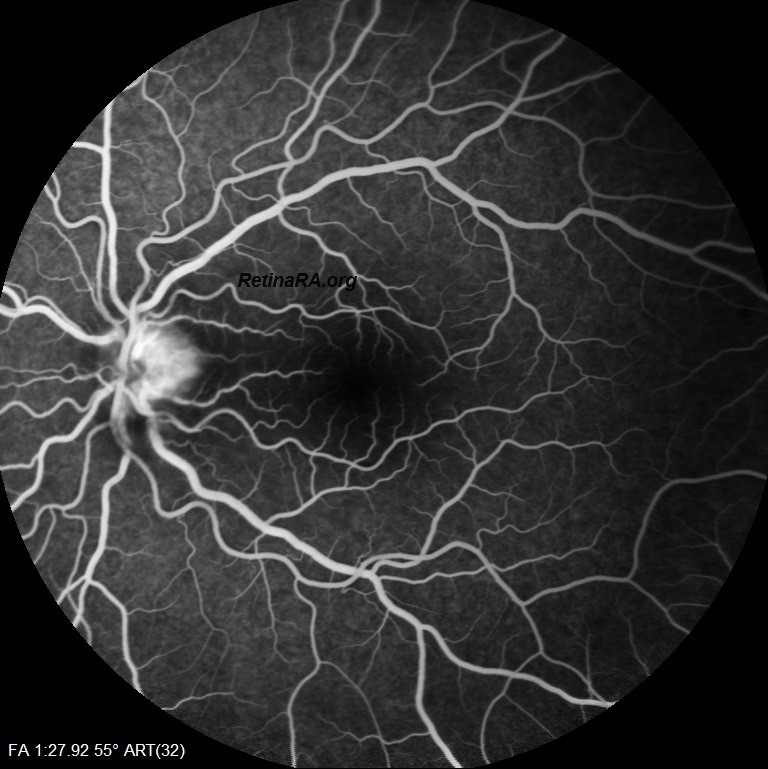

Color fundus photography shows optic nerve head swelling with an infiltrate at temporal margin. This infiltrate appears hyperfluorescent in early and late-phase fluorescein angiography.

Macular edema was also present. The radial stretching lines seen in multicolor imaging and infrared reflectance imaging indicate fluid accumulation in Henle’s fiber layer. Vertical and horizontal OCT B-scans depict Macular edema with subretinal and intraretinal fluid. *Note that intraretinal fluid and exudate particularly accumulated in the Henle’s Fiber Layer. Neuroretinitis is characterized by an inflammation of the optic disc vasculature with exudation of fluid into the peripapillary retina. The lipid-rich component of the exudate is further able to penetrate into the Henle Fiber layer, creating what is clinically seen as a macular star pattern. Only the aqueous phase can pass through the external limiting membrane to accumulate beneath the neurosensory retina.